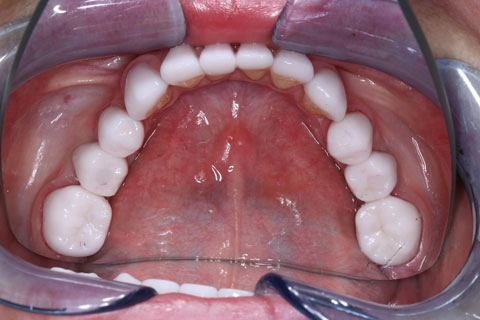

Женщина. 52 года.

Обратилась с жалобами на разрушение зубов 3.6, 4.6, дефекты и дисколорит ранее наложенных пломб. В анамнезе врожденная адентия 1.5, 2.5, 3.5, 4.5

Удалены корни 3.6, 4.6, с одномоментной установкой имплантатов 3.6, 4.6 и забором соединительно-тканного трансплантата с небной поверхности в области 1.6.

Проведена ортопедическая реабилитация.

Фронтальная группа зубов верхней и нижней челюстей – установлены виниры.

Жевательная группа – восстановлена коронками из диоксида циркония, в том числе 3.5, 4.5 – коронки на имплантатах.